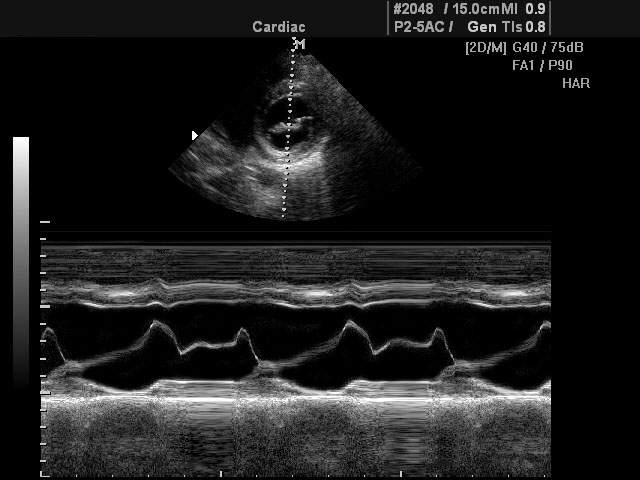

Обзор функций УЗИ: Работа ультразвукового аппарата в М-режиме

M-режим разработан специально для исследований подвижных структур в реальном времени (от английского motion - движение). Наибольшее применение М-режим нашел в исследовании структур сердца (оценка размеров, сократительной функции сердца, работа клапанного аппарата и т.д.).

При помощи M-эхограммы специалист может количественно оценивать геометрическое смещение подвижных структур и измерять их изменение относительно взаимного положения (просвет в клапанах сердца, изменение размера желудочка и прочее). M-режим зачастую используется вместе с B-режимом (англ. brightness - яркость), во время диагностики врач в B-режиме выбирает необходимый ракурс наблюдения, а затем с помощью курсорной линии на B-эхограмме выбирает направление оси ультразвукового луча для M-режима. Положение датчика фиксируется рукой доктора, после чего включается M-режим.

В М-режиме зондирование периодически повторятся в одном и том же направлении акустического луча. При формировании М-эхограммы в каждом зондировании амплитудная информация об эхо-сигналах с различных глубин отображается в виде отметок различной яркости вдоль вертикальной линии на экране (акустической строки). Следующему зондированию соответствует своя линия, расположенная правее предыдущей, в процессе перемещения столбца с каждым новым зондированием формируется двухмерная М-эхограмма. Положение яркостных отметок по вертикали пропорционально глубине отражающей структуры, например, сердечного клапана.

• Одновременное отображение двухмерной B-эхограммы и M-эхограммы (использование двух режимов одновременно).